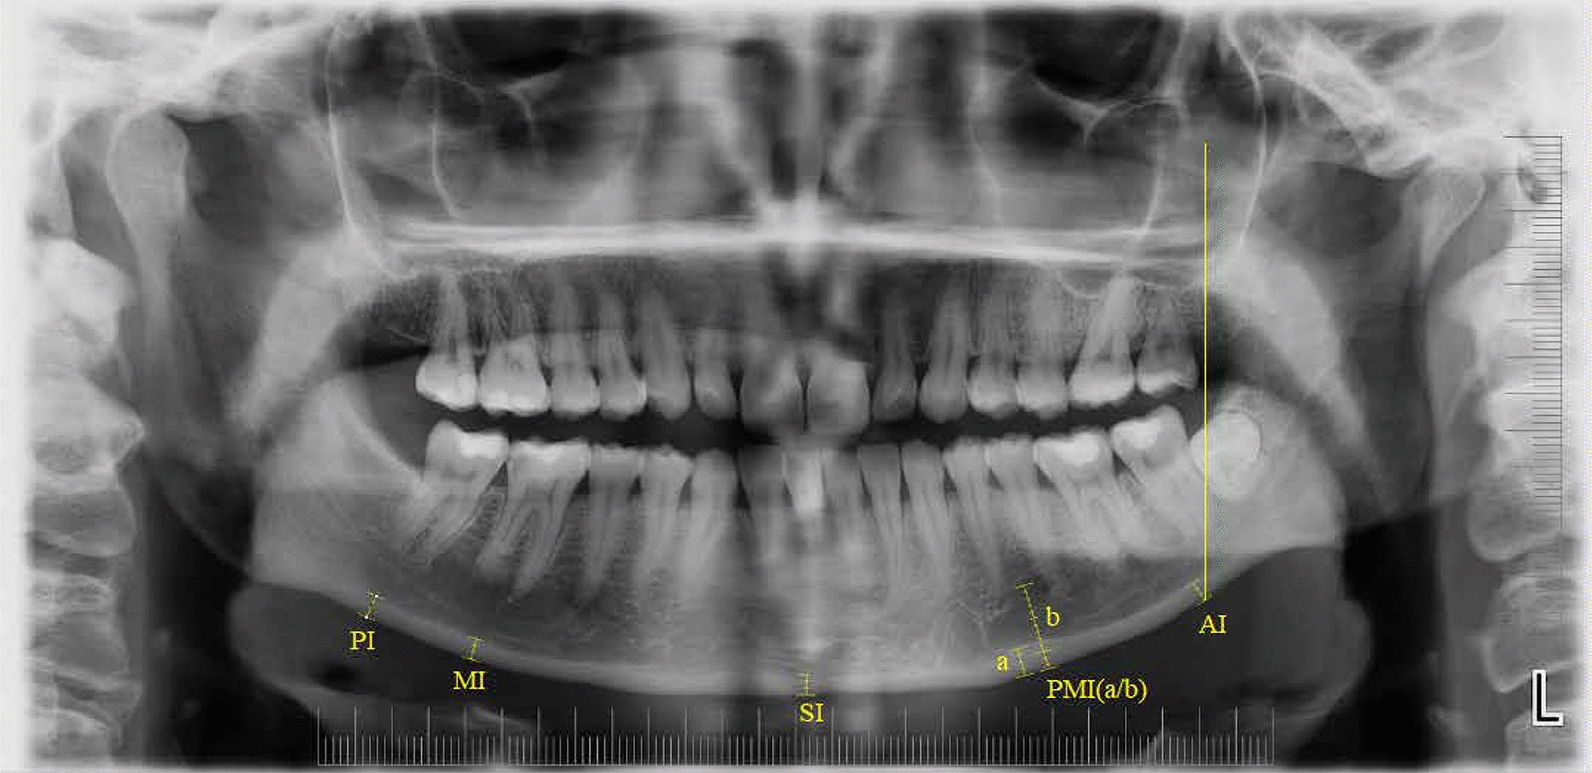

Methods: A retrospective, age- and gender-matched, 3-year longitudinal comparison was performed using 120 panoramic radiographs from 60 individuals (30 PHPT; 30 controls). Each participant contributed baseline and 3-year images (mean interval: 3.26 ± 0.13 years). Radiomorphometric indices (SI, MI, AI, PI, PMI) and FD from three standardized regions of interest (ROI1: condyle; ROI2: angle; ROI3: mental) were measured. Intra-observer reliability was excellent (ICCs 0.80-0.96). Between-group and within-group comparisons used Mann-Whitney U and Wilcoxon signed-rank tests (two-sided, p < 0.05).

Results: The antegonial index (AI) was lower in PHPT than controls at baseline (3.26 ± 0.43 vs. 3.62 ± 0.81 mm; p = 0.034) and remained lower at 3 years (3.24 ± 0.35 vs. 3.55 ± 0.43 mm; p = 0.050). Other indices (SI, MI, PI, PMI) showed no between-group differences at either timepoint and no significant within-group change (all p > 0.05). FD analysis showed a lower ROI2 (mandibular angle) value in PHPT at baseline (p = 0.050) and a significant difference at 3 years (p < 0.01); ROI1 and ROI3 did not differ between groups at either timepoint and exhibited no temporal change (all p > 0.05).